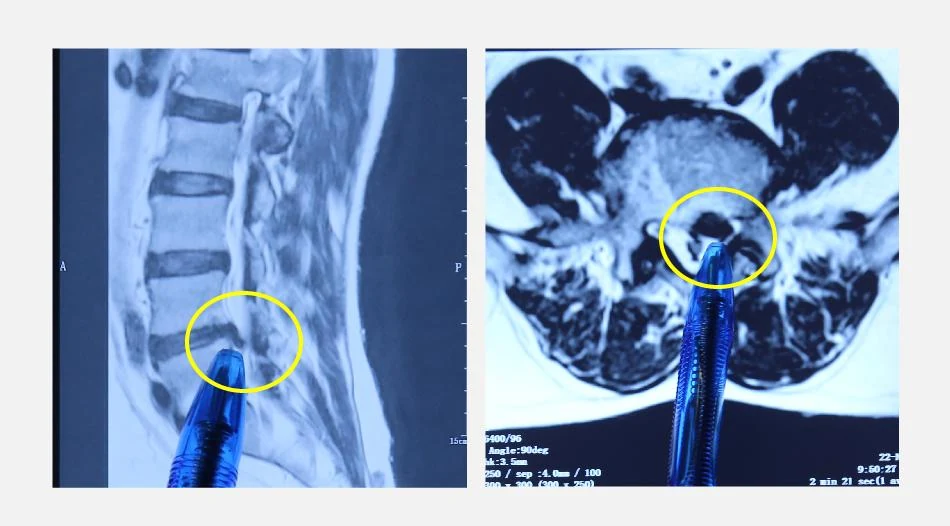

Người bệnh đến kiểm tra tại Khoa Ngoại yêu cầu trong tình trạng đau nhiều vùng lưng, đi lại khó khăn. Sau khi được bác sĩ thăm khám và chỉ định làm các kiểm tra chuyên sâu, người bệnh được chẩn đoán bị hội chứng thắt lưng hông do thoát vị đĩa đệm cột sống thắt lưng.

Hình ảnh phim chụp của người bệnh.

Người bệnh được bác sĩ tư vấn phương pháp điều trị hiện đại và tối ưu nhất là phẫu thuật nội soi hai cổng để giải phóng các rễ dây thần kinh trong ống sống bị chèn ép.